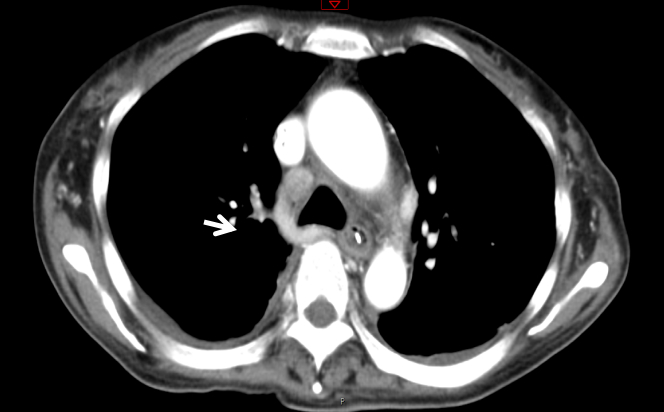

入室诊断:发热查因:结节病?腹膜炎,肺部感染。处理措施包括应用抗生素前行病原学检查;暂予泰能及替考拉宁抗感染,并加强支持治疗。但病情改善不明显。入院第4天(2020-01-21)收到血及腹水培养结果:马尔尼菲篮状菌。修正诊断:马尔尼菲篮状菌感染;肺部感染;腹腔感染;肝功能损伤;胸腔积液;腹腔积液。立即给予两性霉素B治疗。首剂15 mg, 每日增加5 mg, 第4日30 mg, 同时患者热退,胸腹腔积液减少,肝功能好转,凝血功能紊乱纠正,PLT稳步提高。2020-01-31转到呼吸科进一步治疗,两性霉素B疗程满2周,累计量480 mg后序贯伊曲康唑口服治疗,治疗12 d后纵膈淋巴结缩小,患者痊愈出院,出院前CT检查见图 4,WBC等指标变化见图 5。

| 图 4 出院前2020-02-03 CT检查影像示纵膈变化 |